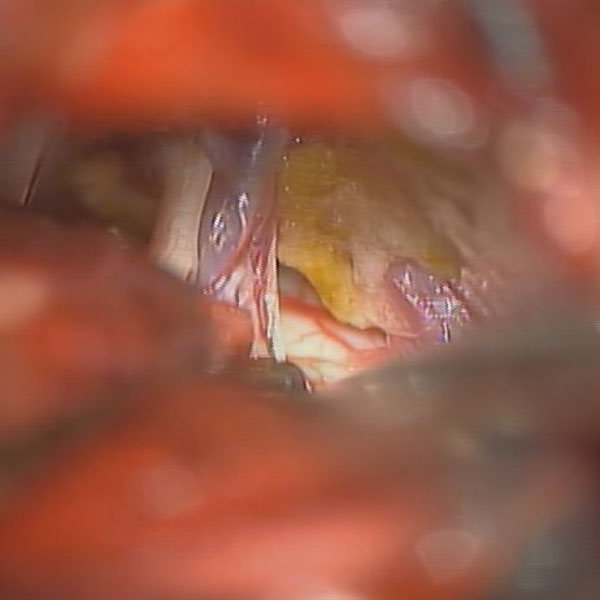

手術中

処置前

処置後